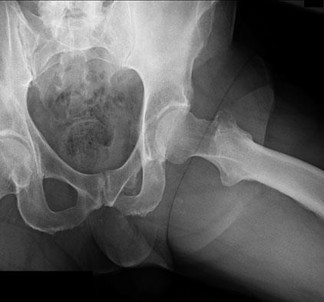

A 15-year-old male presents with deep knee pain awakening him at night. Radiographs show a permeative destructive lesion in the distal femoral metaphysis with a 'sunburst' periosteal reaction and Codman's triangle.

Biopsy confirms high-grade conventional osteosarcoma. What is the most critical prognostic factor for long-term overall survival in this patient?